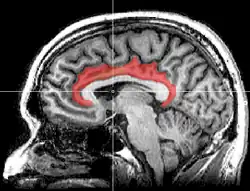

Gyrus cinguli

(der Gyrus cinguli, der relativ zentral liegt, ist orange hervorgehoben)

Der Gyrus cinguli[1] (von lateinisch gyrus ‚Windung‘ und cingulum ‚Gürtel‘) oder Gürtelwindung ist ein Teil des Gehirns und gehört funktionell zum limbischen System. Es handelt sich um eine Struktur des Telencephalons (Endhirn), oberhalb des Corpus callosum (Balken), die die medial liegenden Teile der Hemisphären miteinander verbindet.